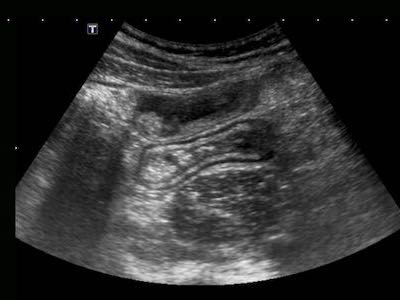

Thông thường, ngay tại lần khám đầu tiên, siêu âm đã bộc lộ “đặc điểm” xuyên thành đặc trưng của bệnh Crohn.

Sự tiến triển xuyên thành này được nhận biết là các thay đổi giảm âm (*) khu trú trong lớp dưới niêm mạc vốn tăng âm, tương quan chặt chẽ với các phát hiện nội soi và các thay đổi mô học viêm hoạt động (4).

Bệnh nhân nam 18 tuổi này nhập viện với các triệu chứng giống viêm ruột thừa cấp và được chụp CT ngay lập tức.

CT cho thấy hình ảnh dày thành hồi tràng rõ rệt và ruột thừa bình thường (không hiển thị ở đây).

Siêu âm tiếp theo cho thấy các thay đổi giảm âm xuyên thành đặc trưng điển hình trong lớp dưới niêm mạc tăng âm, xác nhận chẩn đoán viêm hồi tràng do Crohn.

Lưu ý độ phân giải hình ảnh vượt trội của siêu âm so với CT.

Ở những bệnh nhân có bệnh Crohn hoạt động rõ ràng, cấu trúc siêu âm bình thường của thành ruột có thể bị mất lan tỏa.

Lưu ý mô mỡ tăng âm (fat) xung quanh hồi tràng, đại diện cho mạc treo và mạc nối đang viêm, đang cố gắng bao bọc lại vị trí thủng sắp xảy ra.

Trong những trường hợp như thế này, hình thái thay đổi và lòng ruột hẹp lại có thể bắt chước hình ảnh ác tính.